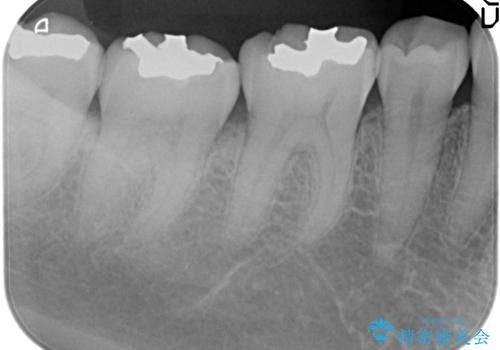

- 右下6番目の歯の舌側に虫歯があるので治療して欲しいといらっしゃった方の症例です。

古い銀歯及び虫歯を除去後、セラミックインレーにて修復を行いました。

虫歯治療は虫歯の進行度によって処置が変わってきます。

虫歯が小さければ、インレー・クラウン等による修復・補綴処置を行うだけで済みます。

しかし虫歯が大きくなると神経処置や抜歯等をしなければならない場合もあります。